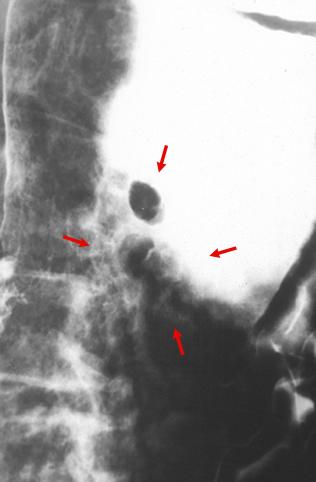

疾患(病理主体)の分類悪性上皮性腫瘍/腺癌

部位(臓器別)胃(部位)/体部

検査方法X-P

腫瘍の肉眼分類0型(表在型)/IIa型(IIa+IIb)

病変の最大径(ミリ)35〜40

腫瘍の深達度m